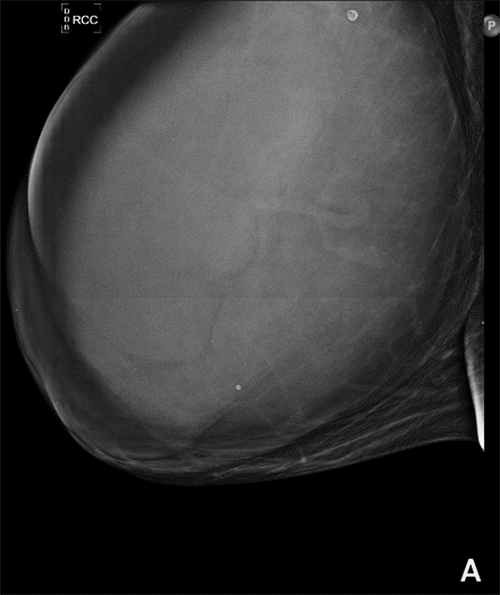

Figure 2. Views of Breast. Published with Permission

A) Right Craniocaudal View of Breast on Mammogram

We present a 46-year-old female with no significant medical/oncologic history who presented to our clinic with a one-year history of an enlarging right breast mass (Figure 1). Family history was significant for breast cancer of unknown etiology in the patient's maternal aunt, who died at age 55. The patient was a premenopausal G2P2 who underwent menarche at age 12, first live birth at age 14, and had no use of oral contraceptives or hormonal replacement therapy. The patient denied any associated symptoms such as breast pain, erythema, nipple discharge, or nipple changes. However, she was unable to wear a bra due to the massive asymmetry between her breasts. She described back pain and the inability to engage in many of her usual activities. She was evaluated with breast ultrasound and mammogram, which revealed a 26 × 22 × 26 cm solid, heterogenous mass with internal cystic spaces occupying all quadrants of her right breast and bilateral lymphadenopathy, with the largest right-sided lymph node measuring 3.5 × 0.9 × 3.3 cm. Ultrasound-guided core needle biopsy of the right breast mass was performed and was consistent with PASH, which was discordant with clinical and imaging findings. Left axillary lymph node biopsy revealed a benign, reactive lymph node. The patient was thoroughly counseled regarding the need for excision and the differential diagnosis included: PASH, phyllodes tumor, sarcoma, hamartoma, or fibroadenoma, and surgical excision was recommended.